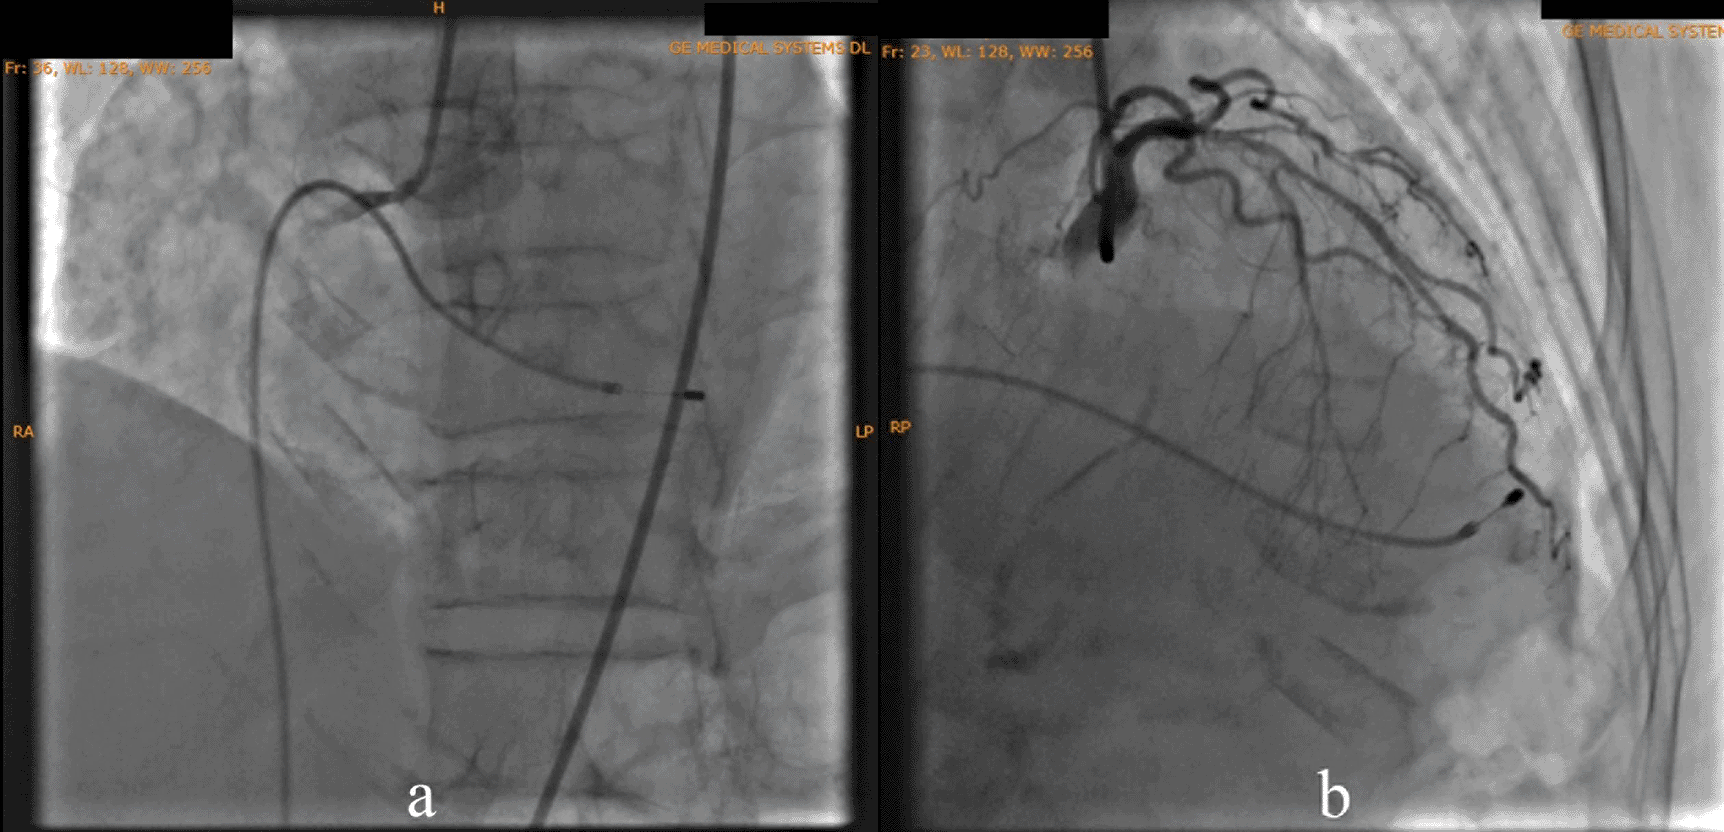

We attached the ECG result during inferior STEMI with TAVB in this patient (Figure 1). We also attached the picture of coronary angiography that clearly show total occlusion of right coronary artery (Figure 2a). We also included the management of TAVB in ACS in the discussion.

According to the DCA, the total occlusion was at the proximal right coronary artery (RCA) (Figure 2). There was insignificant stenosis in the proximal-mid left anterior descending artery. Besides, there were no stenosis on the left circumflex artery and the left main coronary artery. Primary PCI at the RCA was conducted using drug eluting stent (DES) promus and then thrombolysis in myocardial infarction (TIMI) grade 3 flow was shown at the RCA (Figure 3). Electrocardiography was also conducted after the installation of the pacemaker (Figure 4).